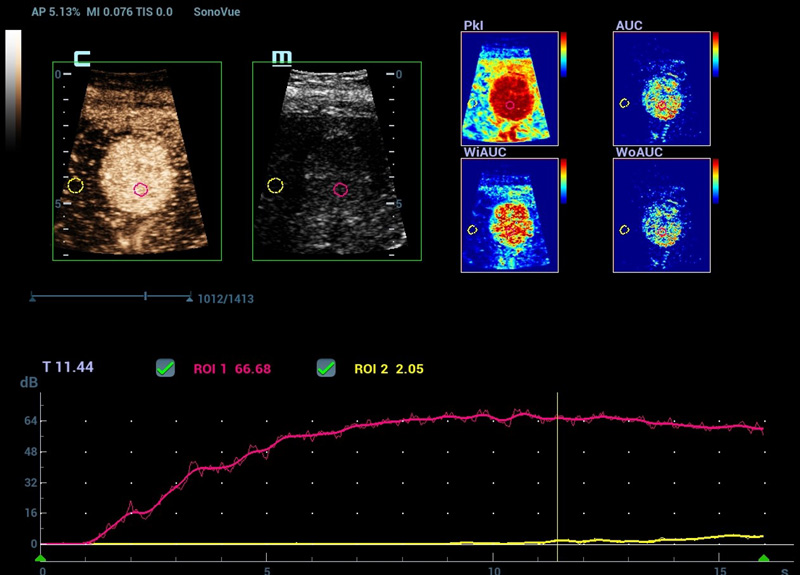

Nova CEUS QA (anûÀlise de quantifica??o)

Ferramentas de ponta para quantifica??o do CEUS

Nova anûÀlise de quantifica??o do CEUS

CEUS QA ã Tumor maligno de mama

A curva tempo-intensidade permite a anûÀlise quantitativa das imagens de CEUS. A nova QA CEUS fornece ferramentas de anûÀlise quantitativa de ponta para ajudar na avalia??o de tumores e na pesquisa clûÙnica.